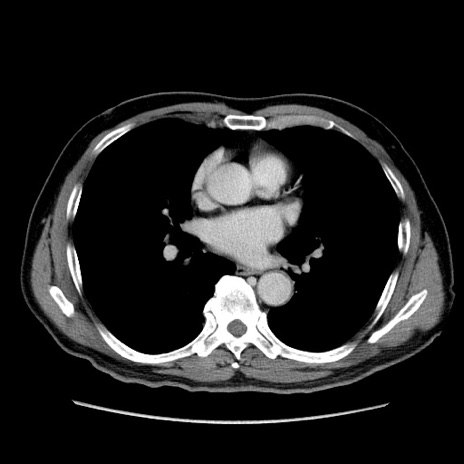

症例34(横断像)

【症例】60歳代 男性

【主訴】右鼠径部膨隆

【現病歴】1年程前より右鼠径部膨隆あり。自己にて還納可能だったため放置していた。3時間前より右鼠径部の脱出を認め、還納困難となり受診。

【既往歴】高血圧

【身体所見】右鼠径部に小児頭大の膨隆あり。弾性硬であり、用手還納は困難。左鼠径部にも膨隆を認める。脱出はなし。

【データ】WBC 15500、CRP 測定なし